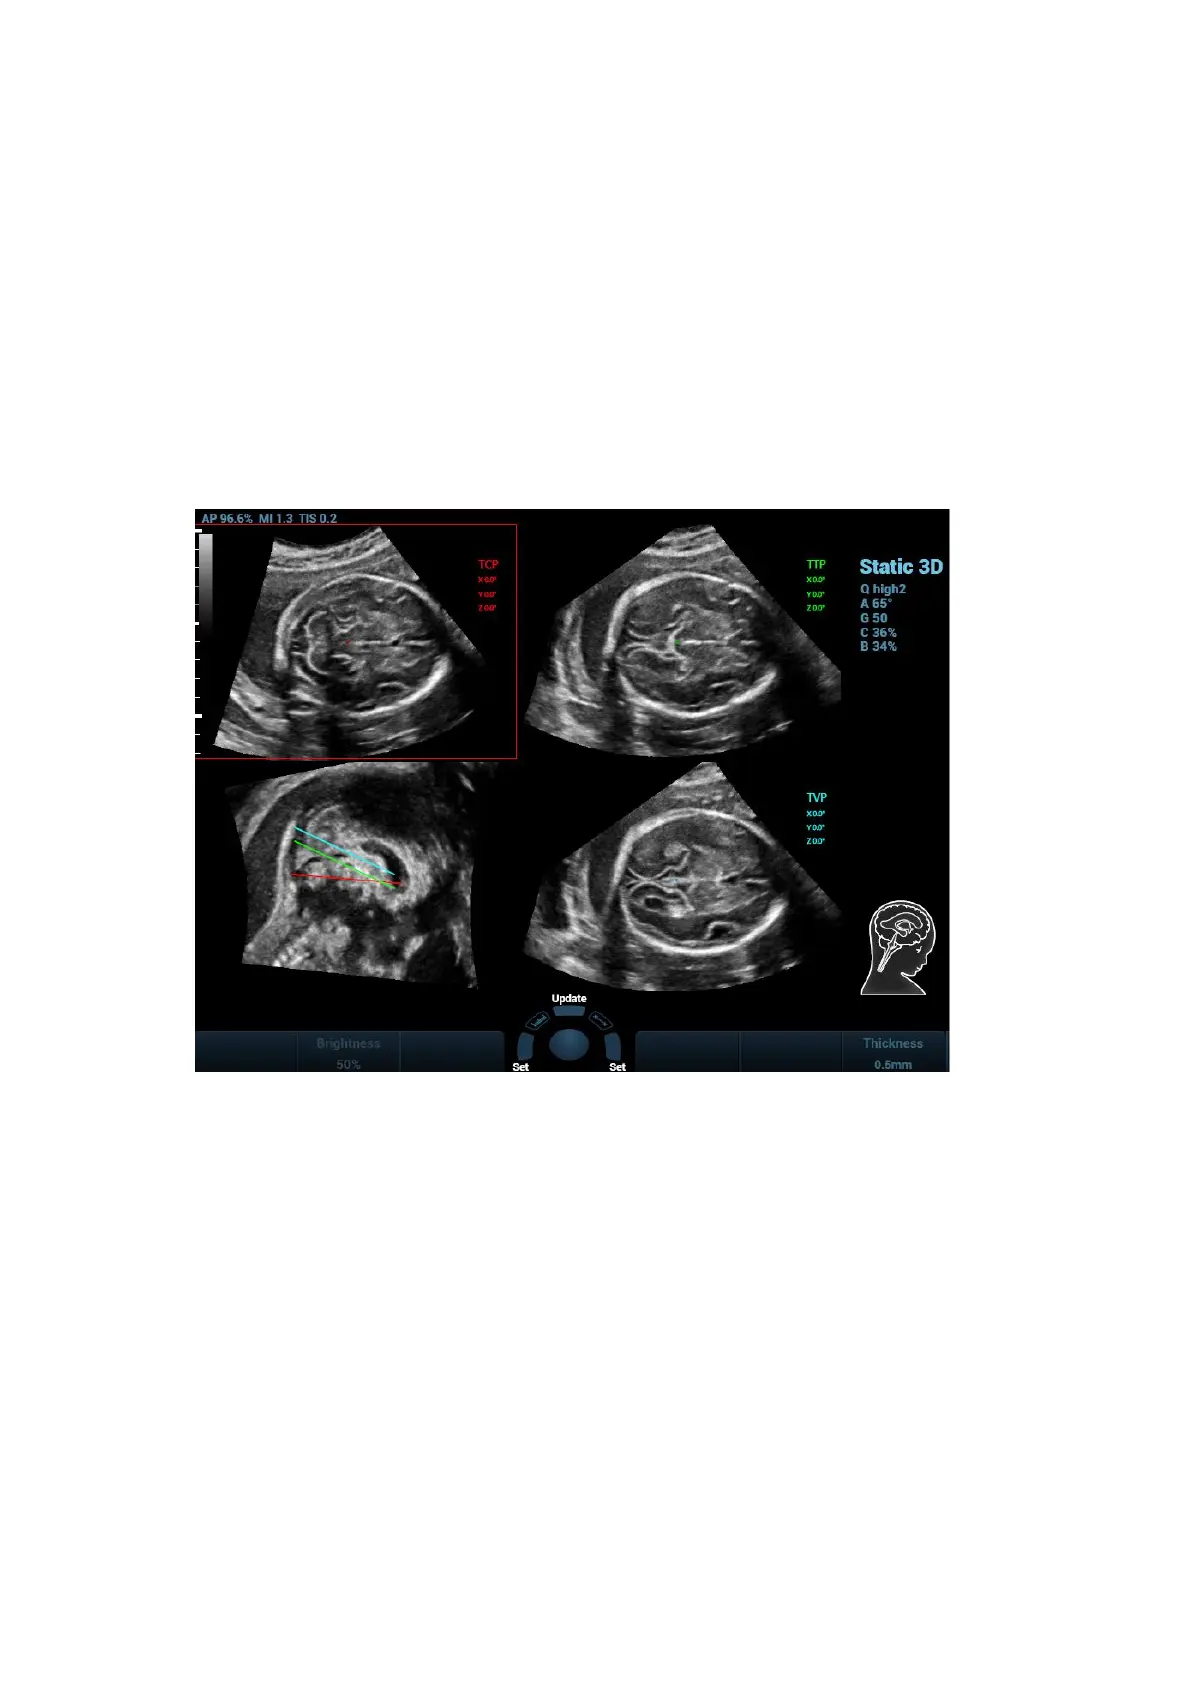

2. Tap [S-Planes CNS]. There are four views detected by the system, which includes TCP, TTP,

MSP and TVP.

3. Adjust the brightness, 3D iClear and the thickness to obtain the image.

4. Tap [MSP]. There are A/B/C images appearing on the screen. The sagittal plane of the fetus

appears on window C.

Rotate A, B or C plane respectively, or rotate <4D> to adjust each plane.